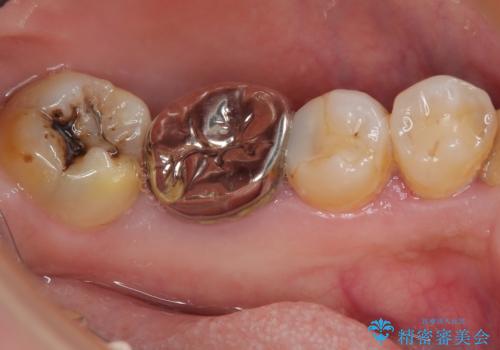

下顎大臼歯の再根管治療とオールセラミッククラウンによる補綴治療

- 10年以上前に治療した銀歯をやり替え希望で来院された患者様です。

噛んだ時に少し違和感があり、レントゲン上で根尖病変が確認できるため再根管治療を行いました。